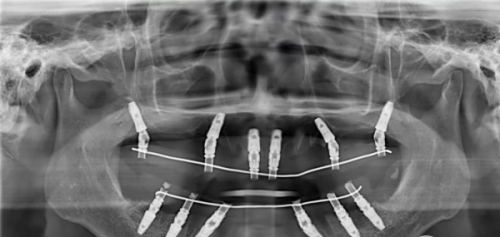

在进行种植牙手术之前,有一系列的准备工作要做。首先,医生会对患者的口腔进行全方面检查,包括口腔X光片、CT扫描等,以了解患者的牙槽骨密度、高度、宽度等情况,确定患者是否适合种植牙。同时,医生还会询问患者的病史,了解患者是否有全身性疾病,如心脏病、糖尿病等,因为这些疾病可能会影响种植牙的成功几率。

植入种植体是种植牙过程的第一步,也是非常关键的一步。在手术过程中,医生会先对患者进行局部麻醉,以减轻患者的疼痛感。然后,医生会在患者的牙槽骨上钻一个小孔,将种植体植入到颌骨内。这个种植体就相当于天然牙齿的牙根,它会与牙槽骨紧密结合,为后续的人工牙提供稳定的支撑。

植入种植体的过程需要医生具备丰富的经验和不错的技术,以确保种植体的位置和角度正确无误。手术时间一般在半小时到一小时左右,具体时间取决于种植体的数量和患者的口腔情况。术后,患者可能会出现轻微的肿胀和疼痛,这是正常的反应,一般会在几天内逐渐缓解。患者需要按照医生的嘱咐进行护理,避免食用实力强的食物,保持口腔清洁。